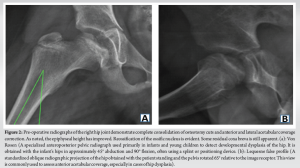

An 8-year-old Hispanic male with no significant medical history presented with bilateral hip pain of eight out of ten on the visual analog scale. He had been followed at a pediatric orthopedic clinic for nearly a year for magnetic resonance imaging (MRI) findings suggestive of bilateral LCP disease at the early fragmentation stage. Lesions were somewhat symmetrical, so a rule out of Meyer’s dysplasia and genetic counseling was done accordingly. Imaging showed 10–15% non-enhancement in the left hip and 10% in the right hip, with more severe avascular necrosis on the right. Scant effusions were noted, without signs of arthrosis or collapse. Given his age and benign diffusion-weighted MRI findings, he was managed conservatively with non-steroidal anti-inflammatory drugs, activity modification, and rest for over a year. Due to persistent pain and unchanged imaging findings, he was referred to our Hip Preservation Clinic. On examination, a functional waddling gait was noted. Bilateral hip flexion was 0–100°, with pain on pure flexion. Internal rotation with flexed hips measured 15° with pain, and external rotation was 40° bilaterally. Anterior impingement and apprehension tests were positive bilaterally. A mucopolysaccharidosis and Sickle Cell panel was ordered and returned negative. Given the benign clinical picture, conservative management continued, including close observation and a 2-month course of physical therapy. At a 4-month follow-up, the patient reported no improvement in pain, and his physical exam remained unchanged. Repeat MRI revealed an under-covered femoral head with a chondral defect partially covered by functional cartilage (Kerboul Grade II) (Fig. 1). A full radiographic workup showed findings consistent with borderline hip dysplasia (Fig. 2), prompting the recommendation for bilateral triple pelvic osteotomies (PAO).